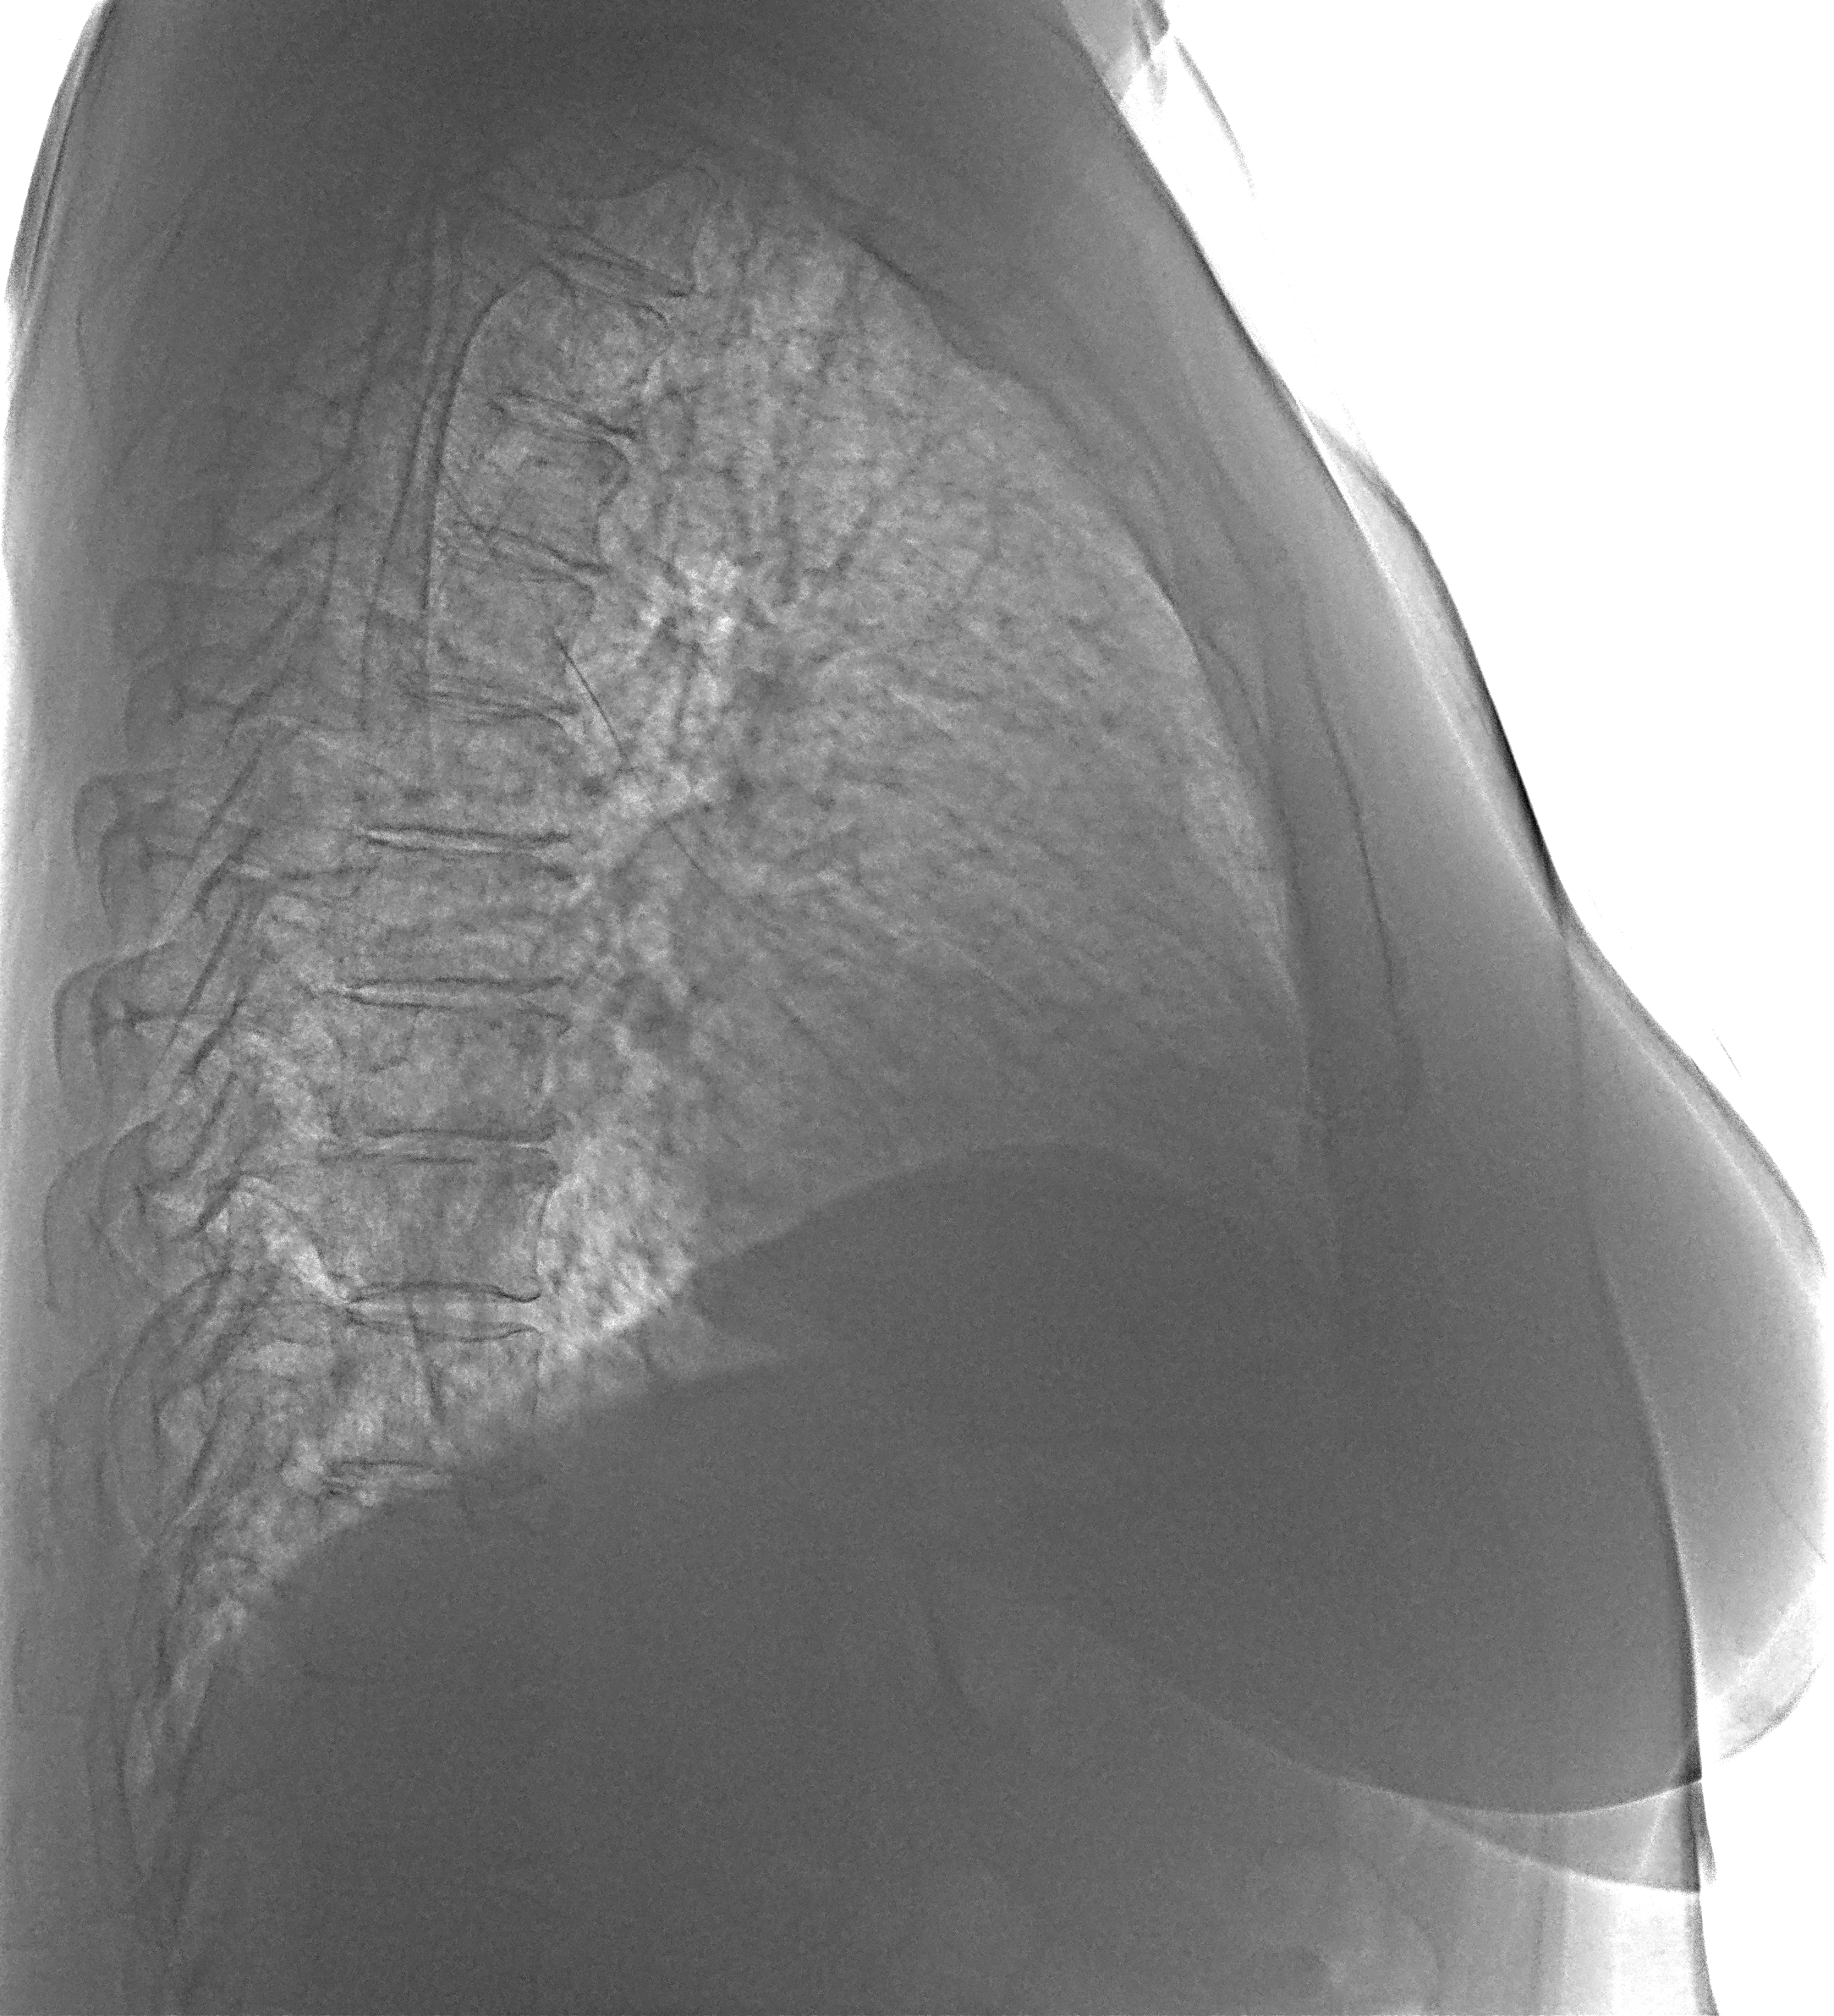

Плеврит по 5 ребру